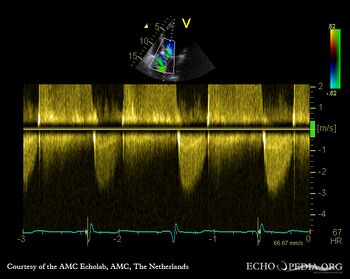

E00343.jpg

E00344.jpg

Continuous-wave signal of transaortic flow, mild aortic valve stenosis Continuous-wave signal of aortic regurgitation